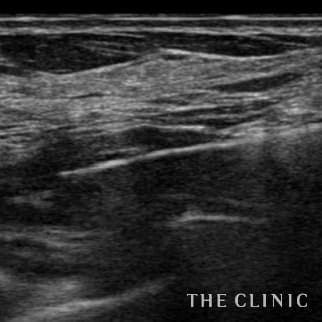

コンデンスリッチ豊胸を行うために、前もってアクアフィリングの除去を行いました。エコーで確認するとかなり厚い被膜が形成されています。 アクアフィリングは生理食塩水で溶解されるとのことで、エコー下に生理食塩水を注入しましたが、なかなか溶解できず、ヒアルロニダーゼも追加してなんとか溶解除去することができました。右側は炎症があった為か、汚く濁った状態でした。治療の概要 アクアフィリング除去+コンデンスリッチ豊胸:乳腺用エコーを用いて、バスト内の状態を確認。その後、生理食塩水でアクアフィリングを溶解する。溶解仕切れない場合には、注射器で吸い出し除去。アクアフィリング の除去後、バストの皮下にコンデンスリッチファット(老化細胞や不純物を取り除いて濃縮させた自己脂肪)を注入。 施術費用 アクアフィリング 除去(会員料金):¥600,000(税込¥660,000)/溶解1部位